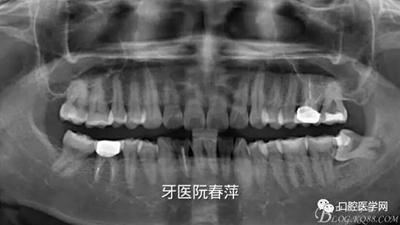

戴牙后全景片:

絢彩AT無飾瓷全形態(tài)氧化鋯產(chǎn)品體驗(yàn)+全冠和嵌體微創(chuàng)修復(fù)后牙

【X光片檢查】

后牙的修復(fù)體X光線阻射應(yīng)該強(qiáng)于釉質(zhì),以方便日后對繼發(fā)齲的檢查。X光片還能從直觀上對修復(fù)體邊緣是否密貼,鄰面有無懸突進(jìn)行進(jìn)一步的檢查。